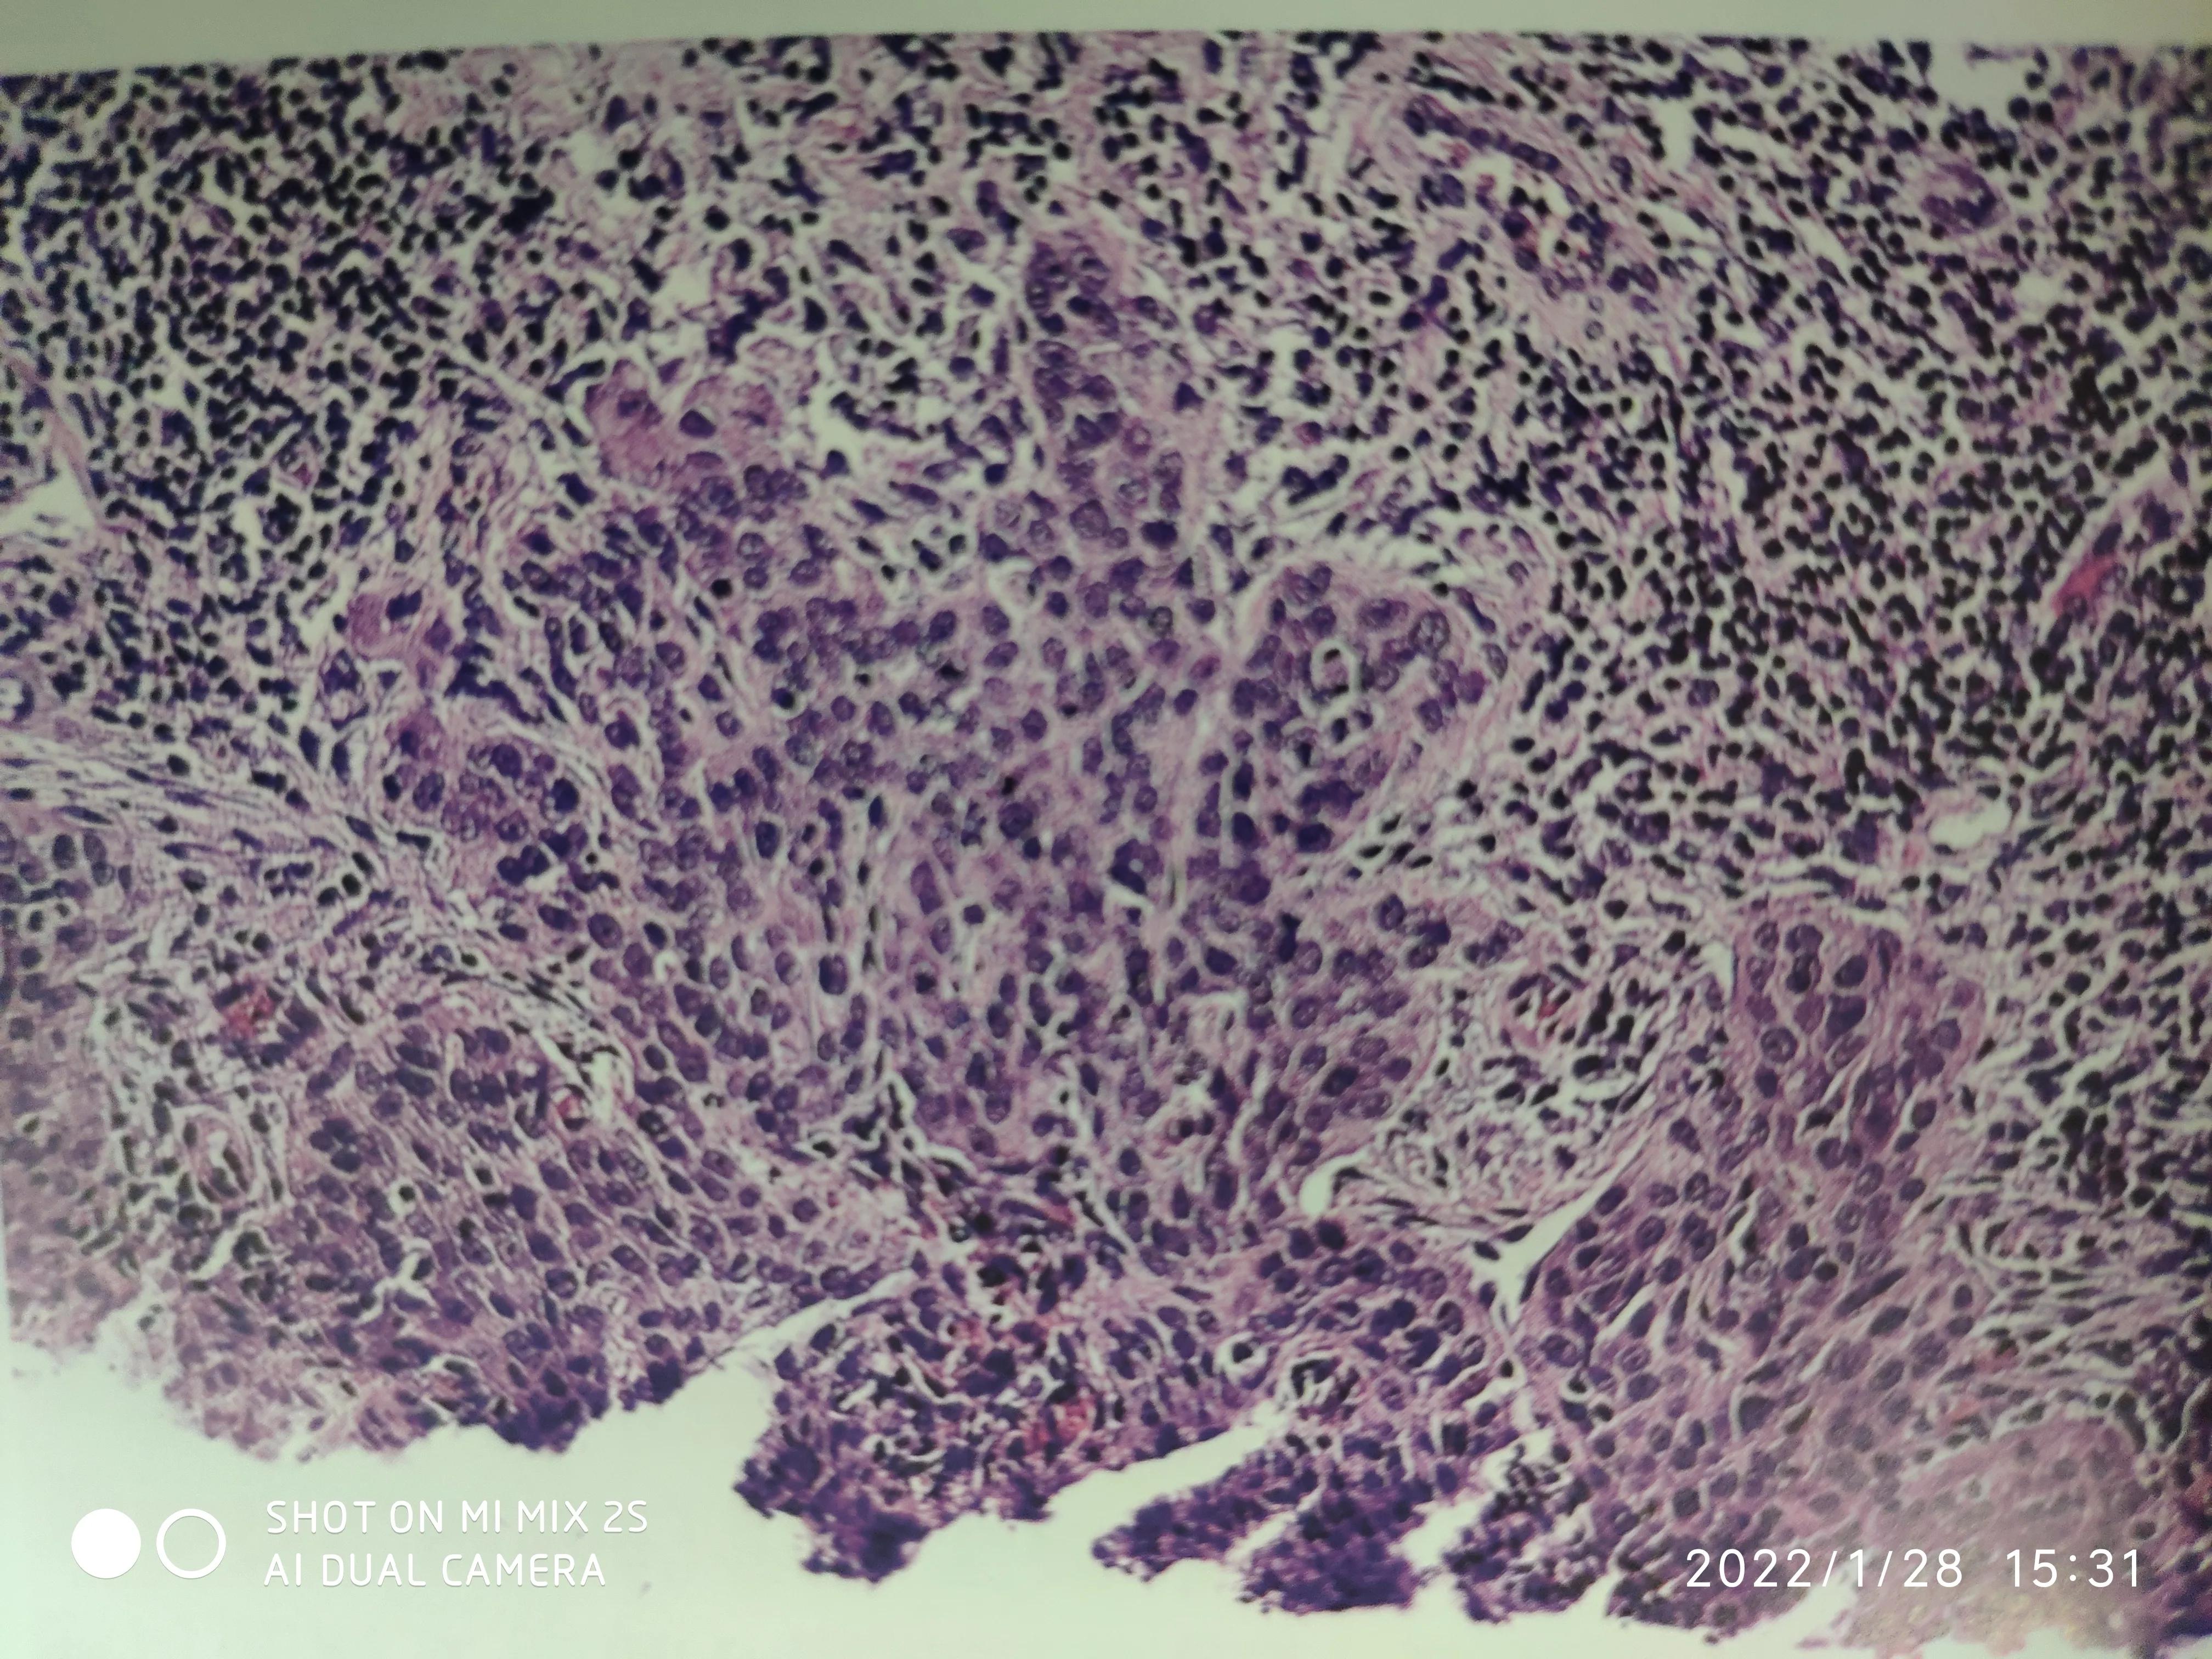

宫颈早期浸润性鳞癌

理论上讲,原位癌是各型癌产生、发展的必须经历的早期阶段,由于原位提供细胞生长所需的养份有限,癌细胞生长缓慢,有些癌可以长期处于原位状态而不再进展,或者进展缓慢甚至达到数年之久,可癌细胞能够产生一些组织酶,不断地降解破坏基底膜,终于有一天突破了基底膜,进入间质,就是常说的发生了浸润,进入了快速生长模式。

由于癌细胞有着超强的增生繁殖能力,且不受机体的反馈性生长调控,间质中丰富的血供,源源不断提供肿瘤生长所需的各种营养成分,随着癌细胞疯狂生长繁殖,可能破坏血管、淋巴管而发生转移,同时癌细胞也会产生大量的肿瘤抗原,激发机体产生抗肿瘤的免疫反应,癌组织周围会出现多少不等的淋巴细胞。